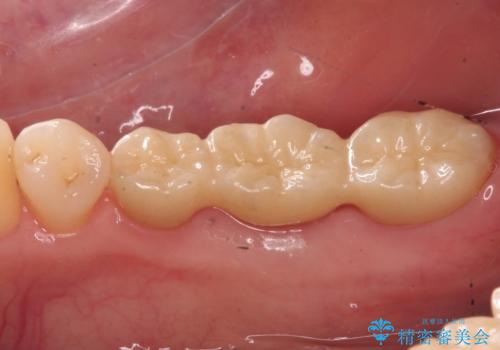

歯がなくなったところに関しては、ブリッジで修復することにしました。

- 26.2万円(ヴェレッツァクラウン 7.7万円×3本 仮歯 1.1万円×3本)費用は治療当時の料金となります